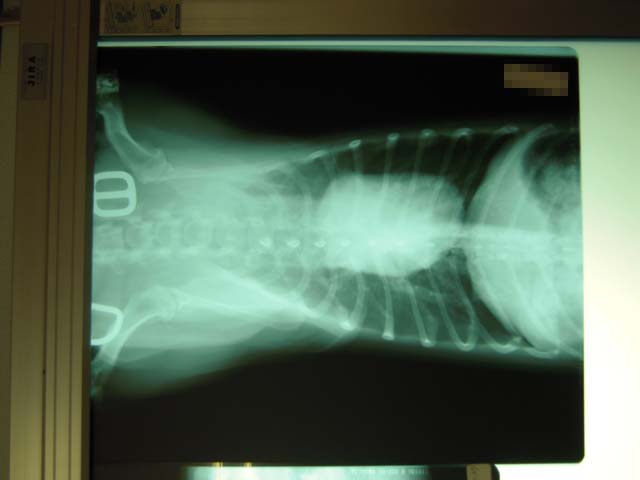

両後ろ足とも手術していますが、冬になるとやっぱり膝の痛みが出やすくなります。走った後に足を少し上げたりするので再度レントゲンでチェック。関 節炎が少しでてきているということです。この写真ではあまりよく見えませんが、関節の間に炎症が少し白っぽく映っていました。足に極度の負担がかかる運動 は注意しないといけません。